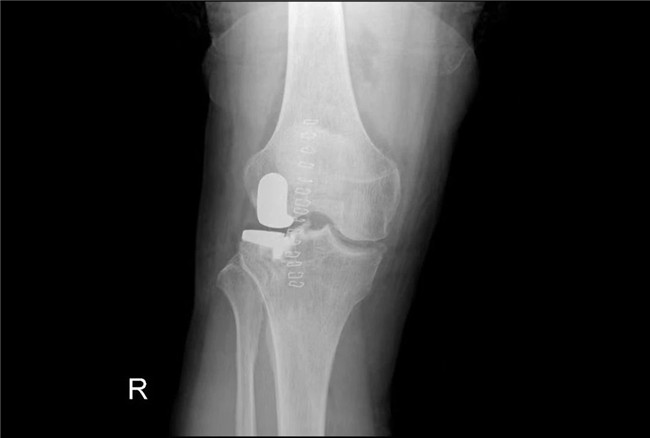

一個單髁置換手術(shù)要想達到理想的手術(shù)治療效果并不簡單,這與假體的大小、方向和松緊度密切相關,其中任何一點出現(xiàn)差池,結(jié)果都會差強人意。為此,羅主任團隊在術(shù)前和術(shù)中進行了精確的設計和測量,制定周密手術(shù)方案,順利為病人實施手術(shù),幫助膝關節(jié)“補牙”。

▲術(shù)后假體位置良好,外側(cè)間隙恢復▲